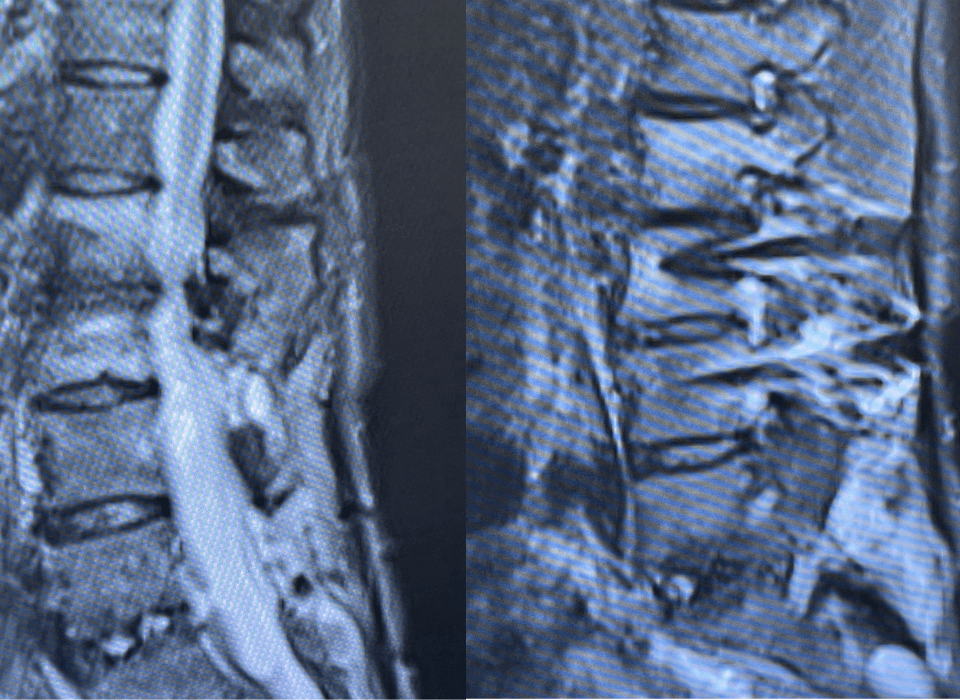

This 62-year-old female presents with chronic intractable low back pain with radiation down the front of her thighs. The patient had had two prior fusion surgeries: […]

“Here’s What Came in Today” by Dr. William Sonstein I specialize in and am very familiar with patients who have osteoporosis and require spinal surgery for […]

I specialize in and am very familiar with patients who have osteoporosis and require spinal surgery for degenerative lumbar disease. I am particularly interested in treating […]